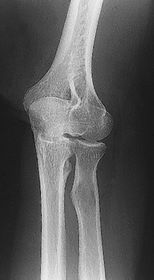

A. humerus B. coronoid fossa C. medial epicondyle D. humeral condyle E. trochlea F. trochlear sulcus G. radial head H. capitulum I. lateral epicondyle J. radial fossa

A. medial epicondyle B. trochlea C. coronoid tubercle D. radial head E. capitulum F. lateral epicondyle H. olecranon process